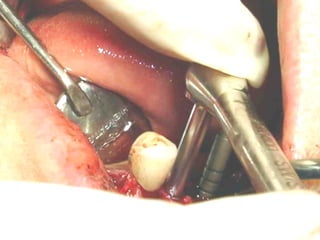

Zacapu 1970

Reimplante ortodóncico

Odontoma

1977

Receptor

Donante

Receptor momento de trasplante

Trasplante 3 meses de evolución